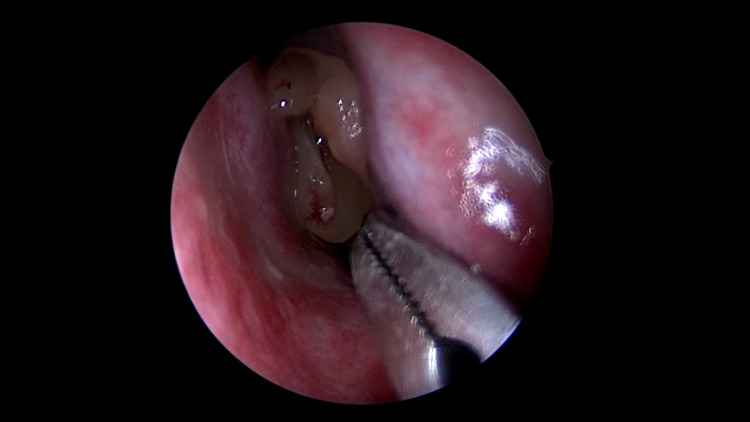

The study was performed on a total of 100 patients, in the department of Otorhinolaryngology, at Chettinad Hospital and Research institute, Chettinad academy of research and education, after getting approved by the Ethical Committee of the Chettinad University. A standard anaesthetic protocol was used for all the patients. After General anaesthesia, the usual physiologic parameters (respiratory rate, pulse rate, blood pressure, and temperature) were monitored during surgery. Standard surgical techniques were performed. Intra-operatively mucosa from nasal and paranasal sinuses, tonsils, and adenoid tissue was collected aseptically for bacteriological investigation (Figs. 1, 2, 3). Patients were extubated and shifted to the postoperative ward.

Fig. 1.

Nasal polyp involving left nasal cavity